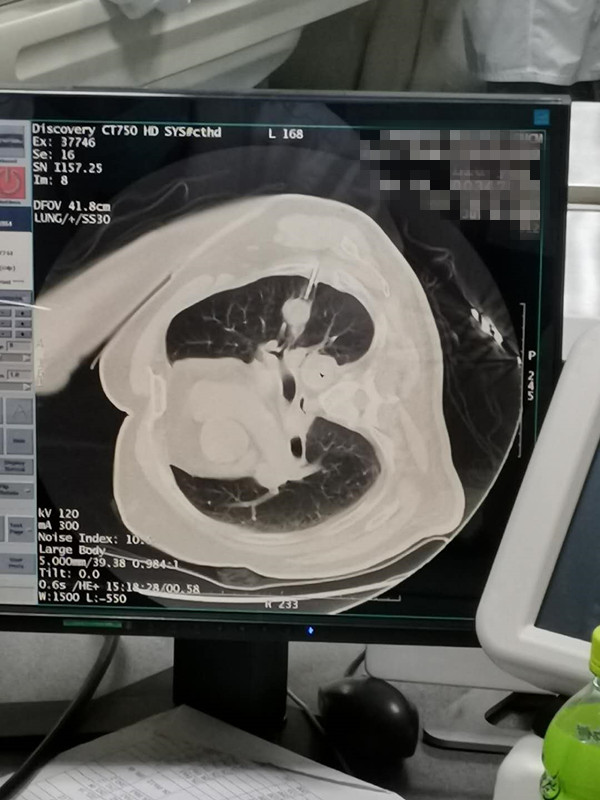

75岁肺部氩氦刀冷冻消融